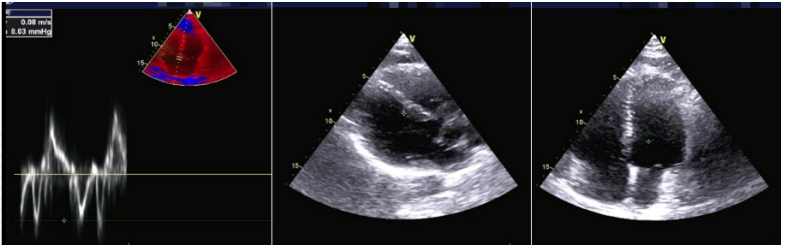

心脏彩超:无任何阳性发现(图3)

图片

3  患者心脏彩超